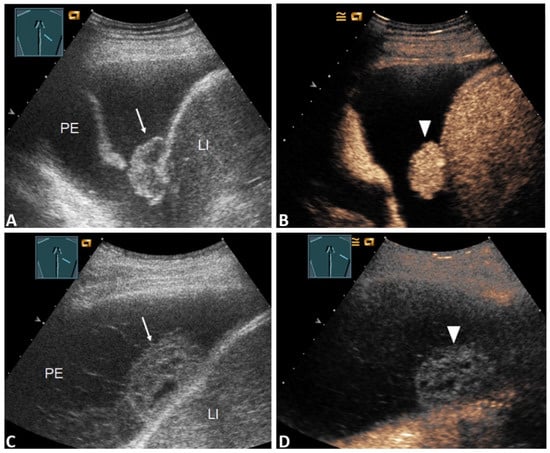

| Pleural thickening with marked enhancement (Figure 2B and Figure 3D) | 27 (32.5%) | 20 (47.6%) | 7 (17.1%) | 0.005 * |

| Pleural thickening with absent or reduced enhancement or no pleural thickening (Figure 3B) | 56 (67.5%) | 22 (52.4%) | 34 (82.9%) | |

| Enhancement of septa or solid formation (Figure 4D) | 2 (2.4%) | 2 (4.8%) | 0 (0.0%) | 0.494 * |

| No enhancement of septa or solid formation (Figure 5C) | 81 (97.6%) | 40 (95.2%) | 41(100.0%) | |